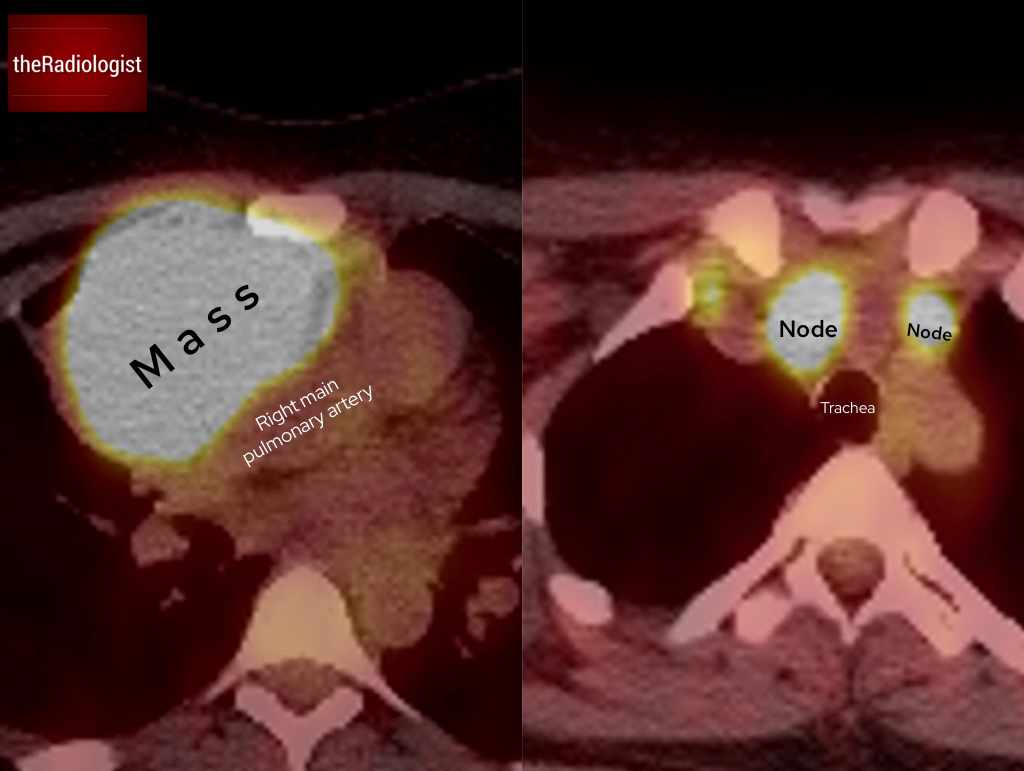

To confirm the nature of this mass, firstly a FDG PET-CT scan was performed showing intense avidity within the lesion and a small number of small lymph nodes within the medistinum, pointing towards lymphoma.

FDG PET-CT shows intense avidity within the lesion and a small number of lymph nodes within the mediastinum.